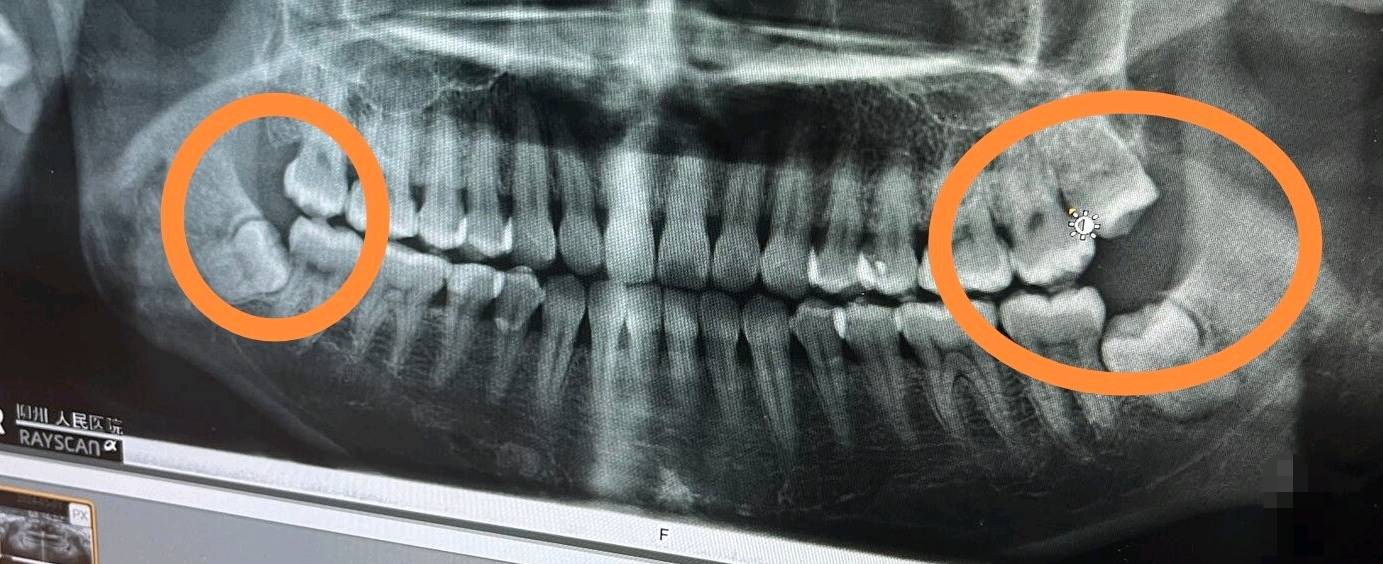

东莞的牙科医院真黑拨一颗牙要一千多,还好没拨!反正一年只要不上火基本不会痛!

你这样的智齿不拔?到时候会把其他牙齿顶歪的,我之前400一颗的,前面没有拔,后面都被顶歪了,多花了一百拔掉的,这个好像可以报销吧

这个价格正常啊,可以去多家医院问下价格,不拔的话会把前面的顶烂的

智牙不拔 把旁边牙顶坏了

我的都长出来 把傍边和上面牙都整坏了